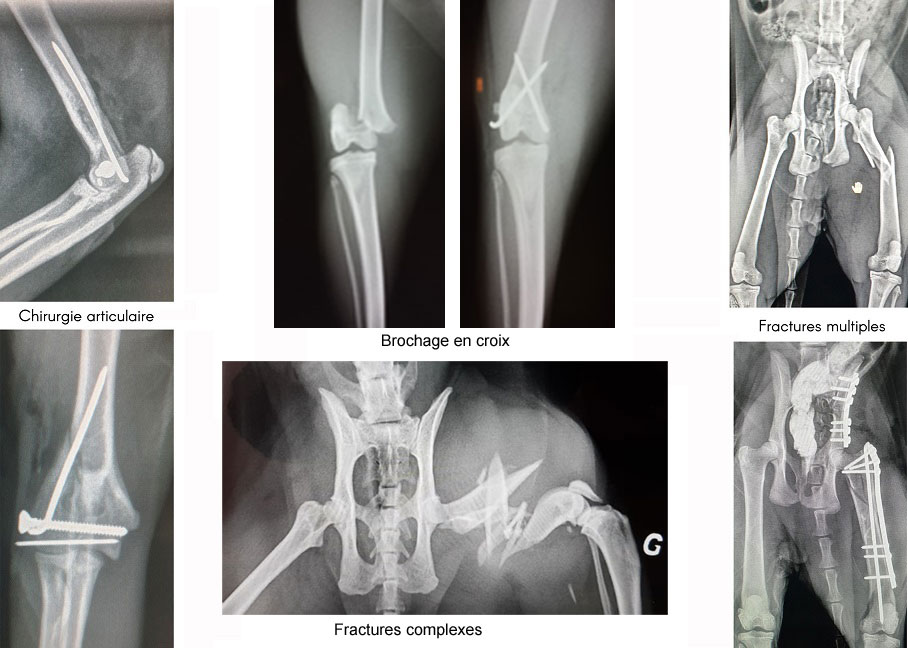

Chirurgie orthopédique

Réparation des fractures, des traumatismes articulaires et des anomalies congénitales

Chirurgie vétérinaire des traumatismes osseux

Fort d'une expérience reconnue en Île-de-France depuis plus de 25 ans, nous nous déplaçons pour réaliser des interventions chirurgicales orthopédiques : pose de plaques vissées, broches, fixateurs externes et prothèses afin de réparer les traumatismes des membres thoraciques et pelviens.